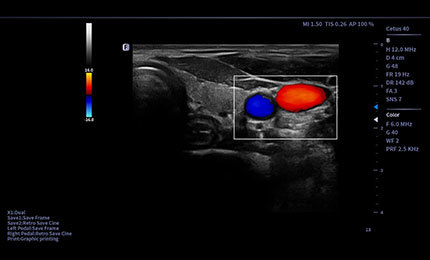

Automatyzacja i wsparcie

Auto Volume Flow

Automatyczny pomiar objętości przepływu krwi na podstawie analizy widmowej oraz obliczeń prędkości przepływu.

8468f1f9 b7a1 4704 a65e 56f811bdafab

Auto IMT

Automatyczna identyfikacja i pomiar grubości kompleksu intima–media (IMT) w naczyniach krwionośnych.